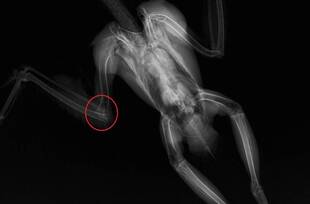

オオタカの肘関節脱臼